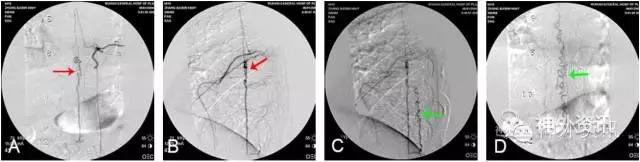

图1: 左侧T9硬脊膜动静脉瘘(SDAVF),↑示瘘口。A. 2D-DSA;B. 3D-DSA;C、D. 最大密度投影(MIP)冠状位与轴位融合影像。

图4: 右T12硬脊膜动静脉瘘(SDAVF),红色↑示瘘口,绿色↑示背侧引流静脉。A. 2D-DSA;B、C. 3D-DSA;D~F. 双容积重建冠状位、矢状位和轴位融合影像。